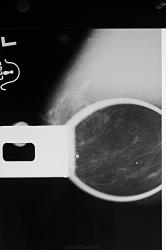

как хорошо виден на прицеле злокачественное узловое образование с микрокальцинатами